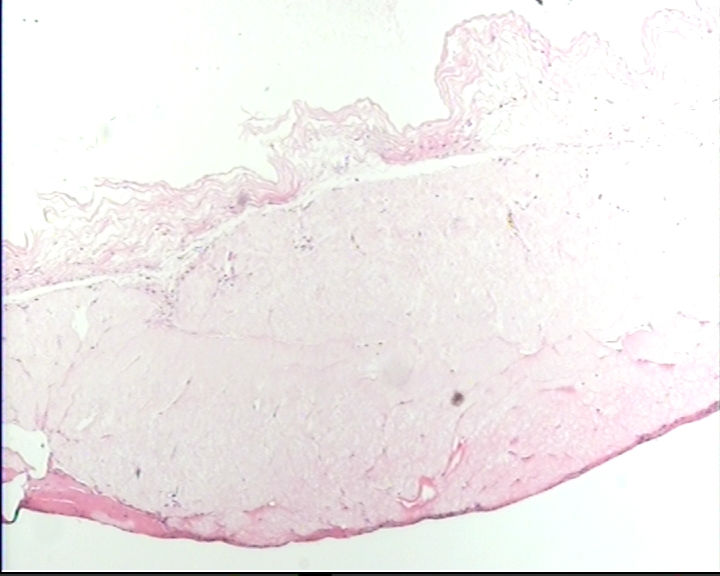

这一类型的卵巢囊肿该怎么发?

剖宫产时卵巢上面剥离下来的,7×6.5×2cm,囊壁菲薄,内容淡黄色清亮液体,内壁光滑

卵巢囊肿图1

仔细找找,如果确实没有明确的被覆上皮就报单纯性囊肿。

单纯囊肿。未见明确上皮成分,良性。

同意单纯性囊肿,没有被覆上皮。

未见被覆上皮,单纯性囊肿。

同意单纯性囊肿,未见明显被覆上皮。